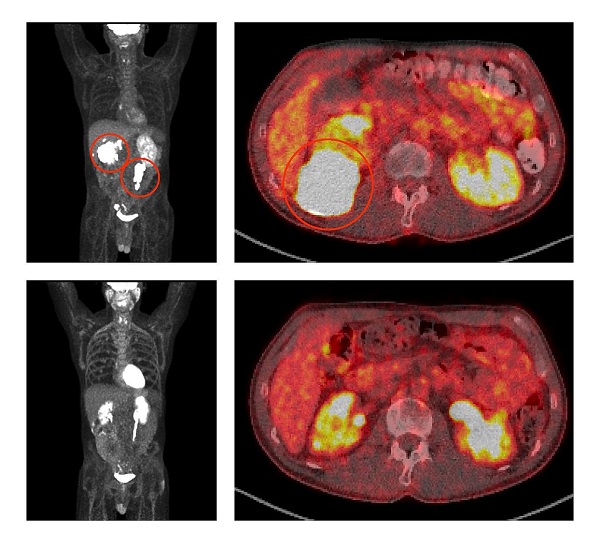

Before treatment with ViPOR, full-body and cross-sectional PET scans of a patient show large lymphoma tumors (circled in the top two panels). Following treatment, the tumors have disappeared (bottom two panels)Center for Cancer Research/National Cancer Institute

June 20, 2024 – Researchers at the National Institutes of Health (NIH) have developed a non-chemotherapy treatment regimen that is achieving full remissions for some people with aggressive B-cell lymphoma that has come back or is no longer responding to standard treatments. The five-drug combination targets multiple molecular pathways that diffuse large B-cell lymphoma (DLBCL) tumors use to survive.